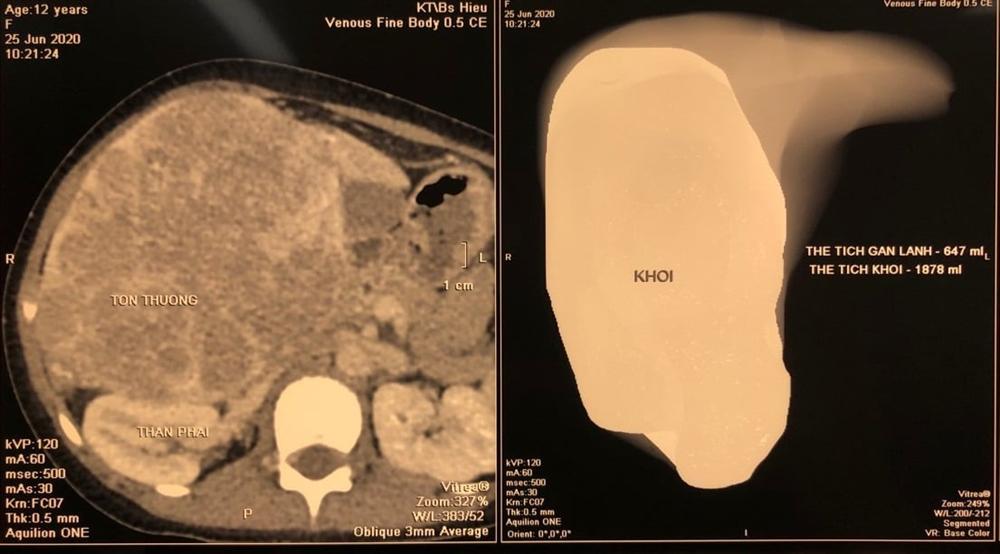

Thông tin từ Khoa Phẫu thuật Gan mật tụy, Bệnh viện Trung ương Quân đội 108, khoa vừa tiếp nhận 1 bệnh nhi 12 tuổi, nhập viện vì bụng to bất thường và có khối u gan to chiếm gần hết vùng bụng.

Bệnh nhi đã được phẫu thuật cắt phần gan phải có chứa khối u. Kết quả giải phẫu bệnh là u nguyên bào gan.

Đa số trẻ ung thư gan thường vào viện với tình trạng bụng to bất thường và có u, sờ được trong bụng. Khối u ở vị trí vùng dưới bờ sườn bên phải hoặc chiếm cả 1/2 bên phải bụng.